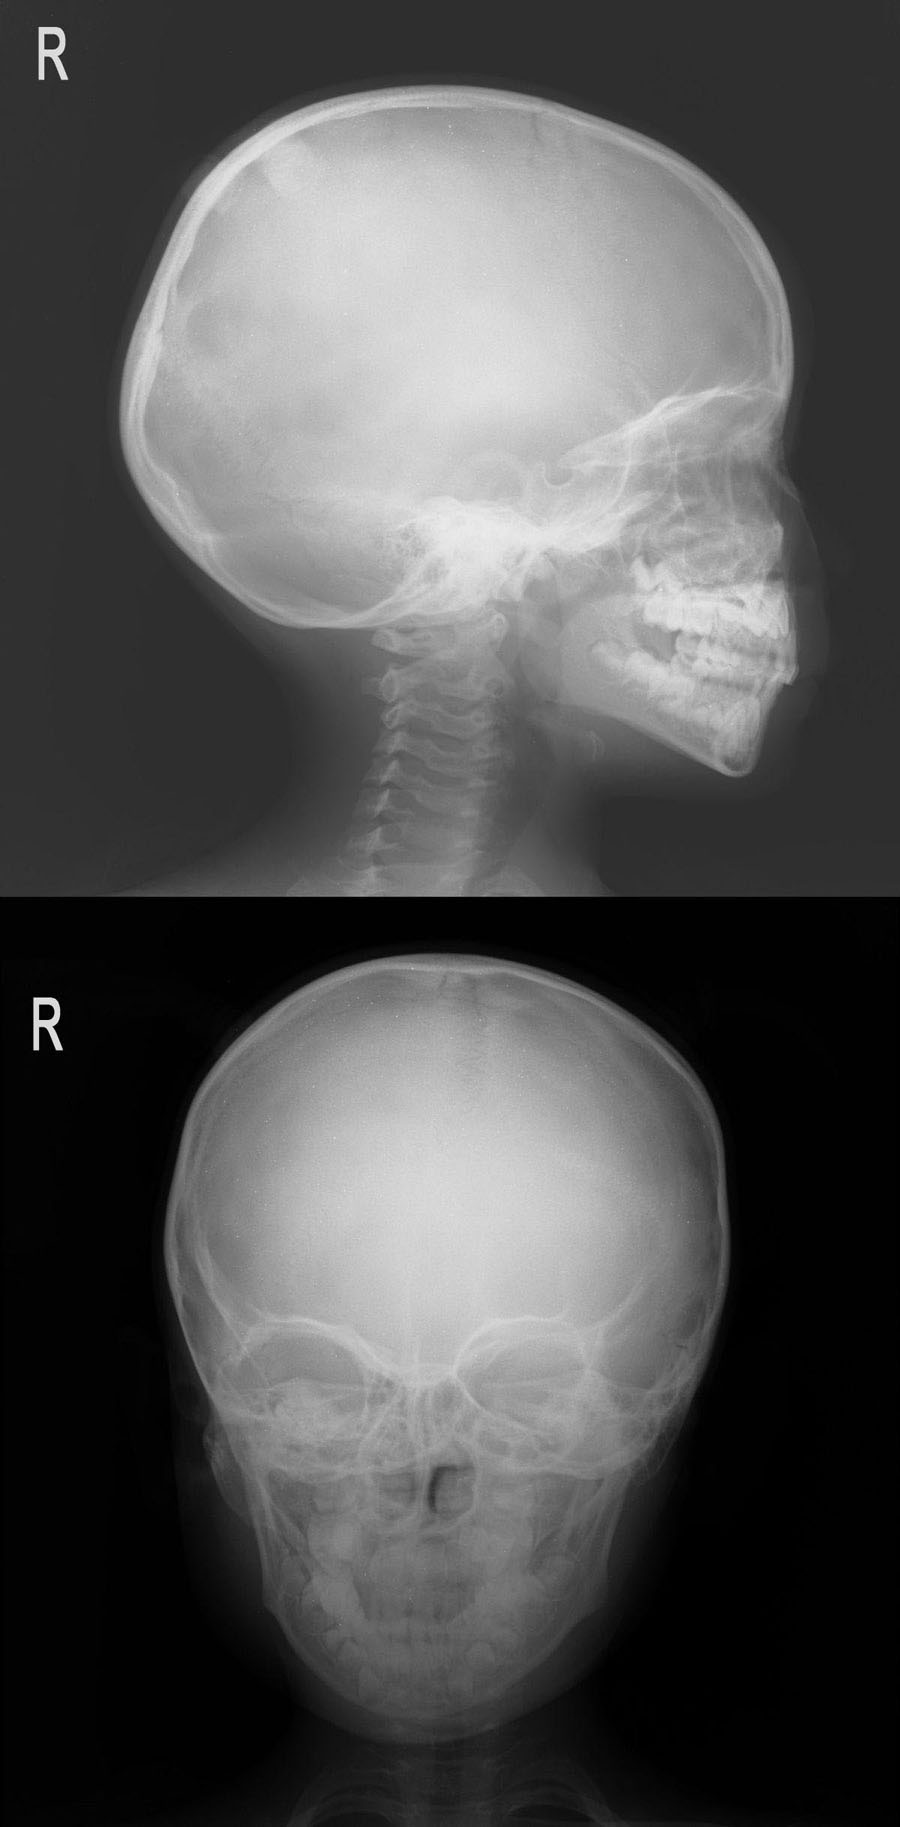

女,7岁,自觉顶部包块,要求cr检查。

类圆形高密度影,边界清楚,无骨质破坏区。考虑骨样骨瘤。应该再照个切线位。

侧位好象有两个致密影,起源于颅板,边缘较光整,,考虑骨瘤可能,高老板呀,好久不见了,你们咋就没照个切线位呢?

顶部类圆形高密度影——扎在一起的头发?

顶部类圆形高密度影,结果为扎在一起的头发,学习了!

顶部类圆形高密度影,结果为扎在一起的头发。